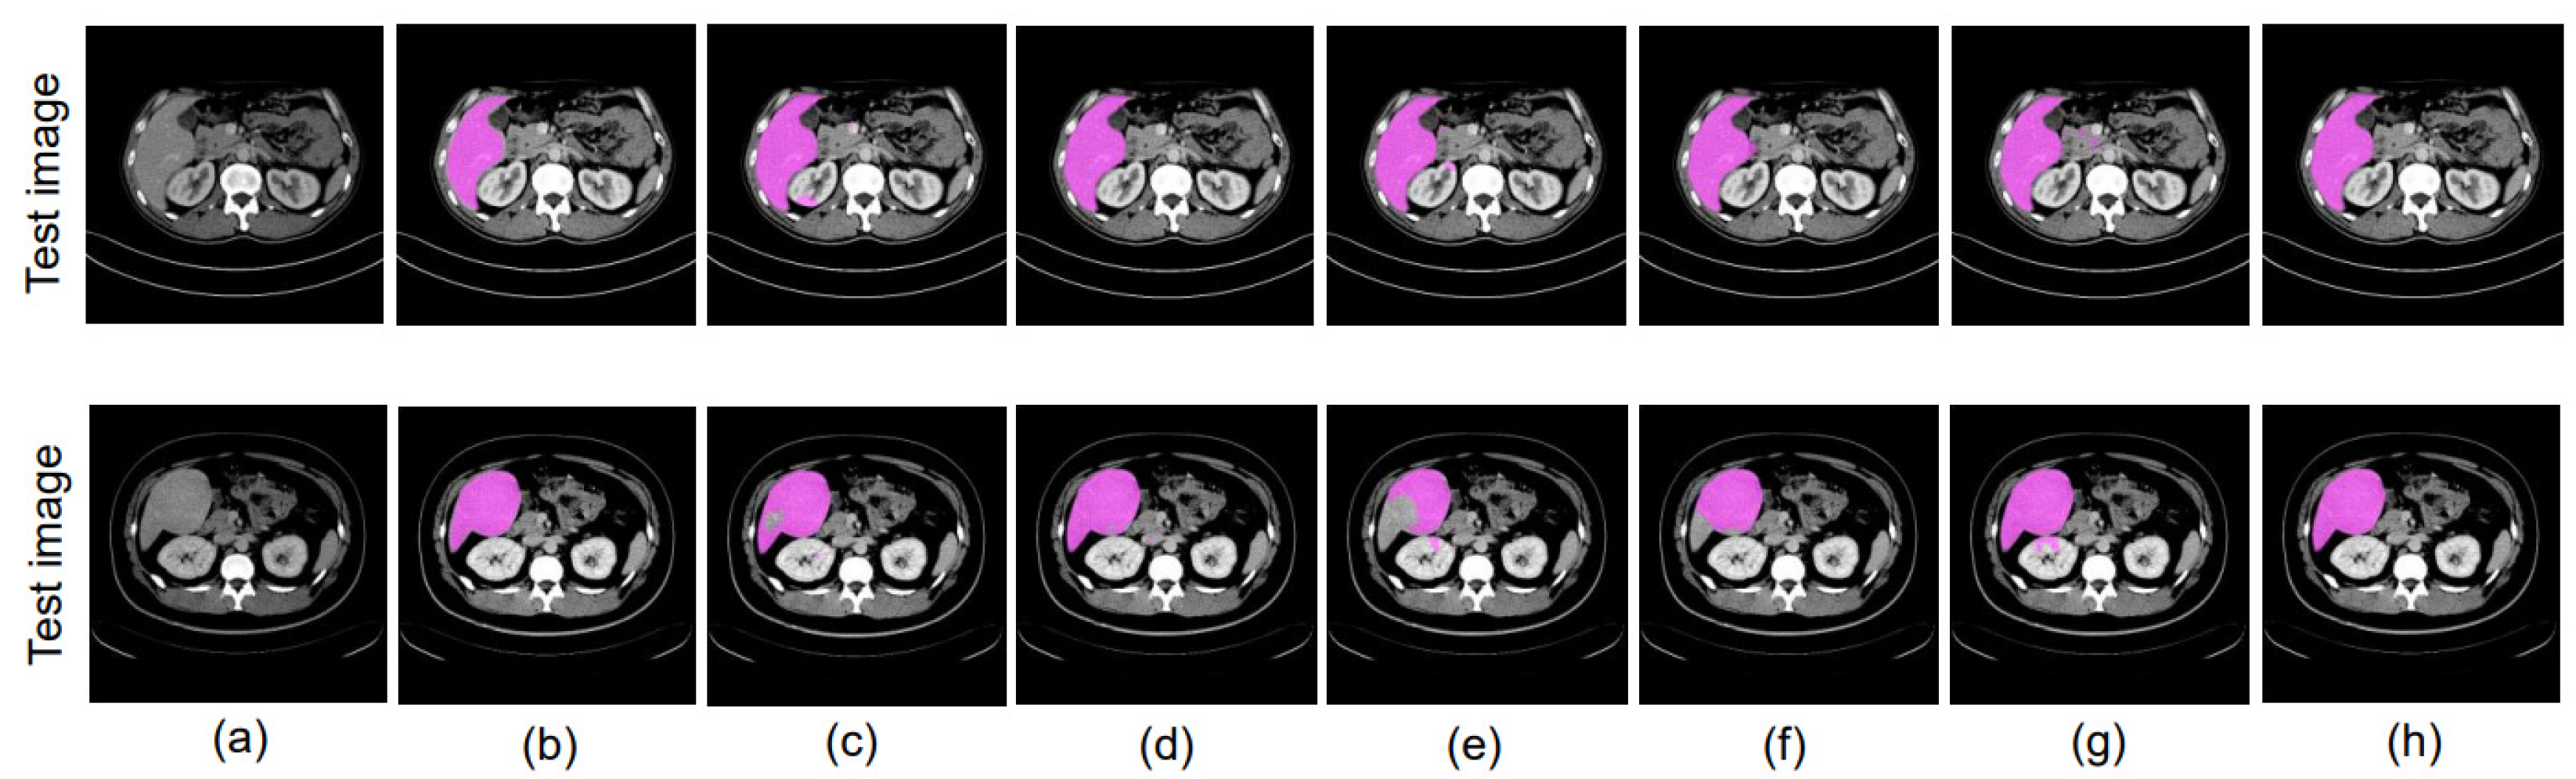

4.8. Ablation Study

4.8.1. Different Datacenter and Same Phase

4.8.2. Same Datacenter and Different Phase

4.8.3. Different Datacenter and Different Phase

4.9. Evaluation of Proposed Methods with SegNet as the Backbone